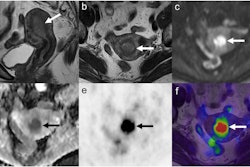

Distribution volumes of a4b2 nicotinic acetylcholine receptors in the brain of normal-weight volunteers and volunteers with obesity. Image courtesy of Swen Hesse, MD.In the resting state, no significant difference in total distribution volume of F-18 flubatine was noted between the groups. However, while viewing photos of food, the total distribution volumes (VT) of F-18 flubatine was higher in obese subjects in the brain's thalamus region where a4b2 receptors are located compared to the control group (28.8 ± 2.1 vs. 25.1 ± 1.9, p = 0.03), according to the findings.